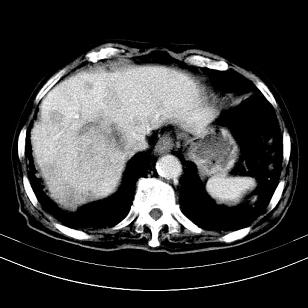

标题: CT19407:肝内还是肝外原发性肿瘤??

男,63岁,高血压病史40余年,

来源-右侧肾上腺。

考虑右侧肾上腺巨大占位;恶性?

肝内多发低密度找;转移瘤?

考虑右肝后叶肝癌(部分外生)伴肝内多发性转移;右侧肾上腺区恶性肿瘤并肝转移待排。

考虑右侧肾上腺肿瘤并肝内多发转移。右侧肾上腺呈“八”字形,包括内侧枝及外侧枝,内侧枝受压,考虑外侧枝原发肿瘤。”

考虑肝右后叶肝癌(部分外生)伴肝内多发性转移;不排除右侧肾上腺区恶性嗜铬细胞瘤并肝转移。